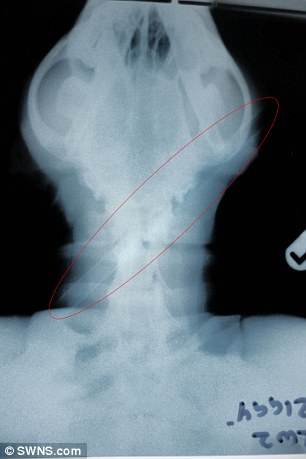

Παρατημένο στο δάσος και με ένα βέλος καρφωμένο στο κεφάλι του βρέθηκε… ένα μικρό σκυλί δύο μόλις ετών στο δάσος του Wansford στο Peterborough.Το βέλος είχε διαπεράσει το κρανίο του Ziggy, ενώ για χιλιοστά δεν είχε διαλύσει κυριολεκτικά τον εγκέφαλό του.

Ο κτηνίατρος Justin Stubbs μετά την εγχείρηση, σημείωσε χαρακτηριστικά ότι «παρά το γεγονός ότι το βέλος διαπέρασε το κρανίο του Ziggy, με έναν απίστευτο τρόπο δεν πείραξε τον εγκέφαλο, ούτε κάποιο νεύρο που να επηρεάσει την όραση ή την ακοή του. Όταν το διαπίστωσα δεν μπορούσα να το πιστέψω».